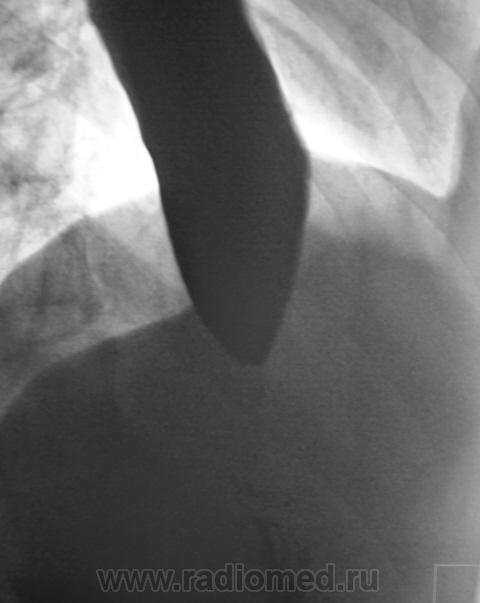

Пациент направлен на рентгенологическое исследование ЖКТр из военкомата с диагнозом - "Хронический гастрит". Пациенту неоднократно проводилась ФГДС. В течение последник 6 лет наблюдается и обследуется в области по поводу хронического гастрита и невроза пищевода. Произведено стандартное исследование.

"Картинка" через 1 час после приема водной взвеси сернокислого бария.

И еще "картинка" через 15 минут.

Все эластично, все смещаемо.

При обзоре газа в газовом пузыре не было.

Ахалазия пищевода.

Или спазм кардии, хотя ахалазия более подходит.

Направлен "от военкомата" - 17 лет. Мальчик худоват. На мой вопрос по поводу жалоб ответ был интересный - "после приема любой пищи - срыгиваю". Именно "срыгивает". Ест малыми порциями. Невроз и гастрит приклеены, как диагноз, в течение 6 лет.

классика ахалазии кардии, 3 ст. симптом  "мышинного хвоста".

Ахалазия кардии.